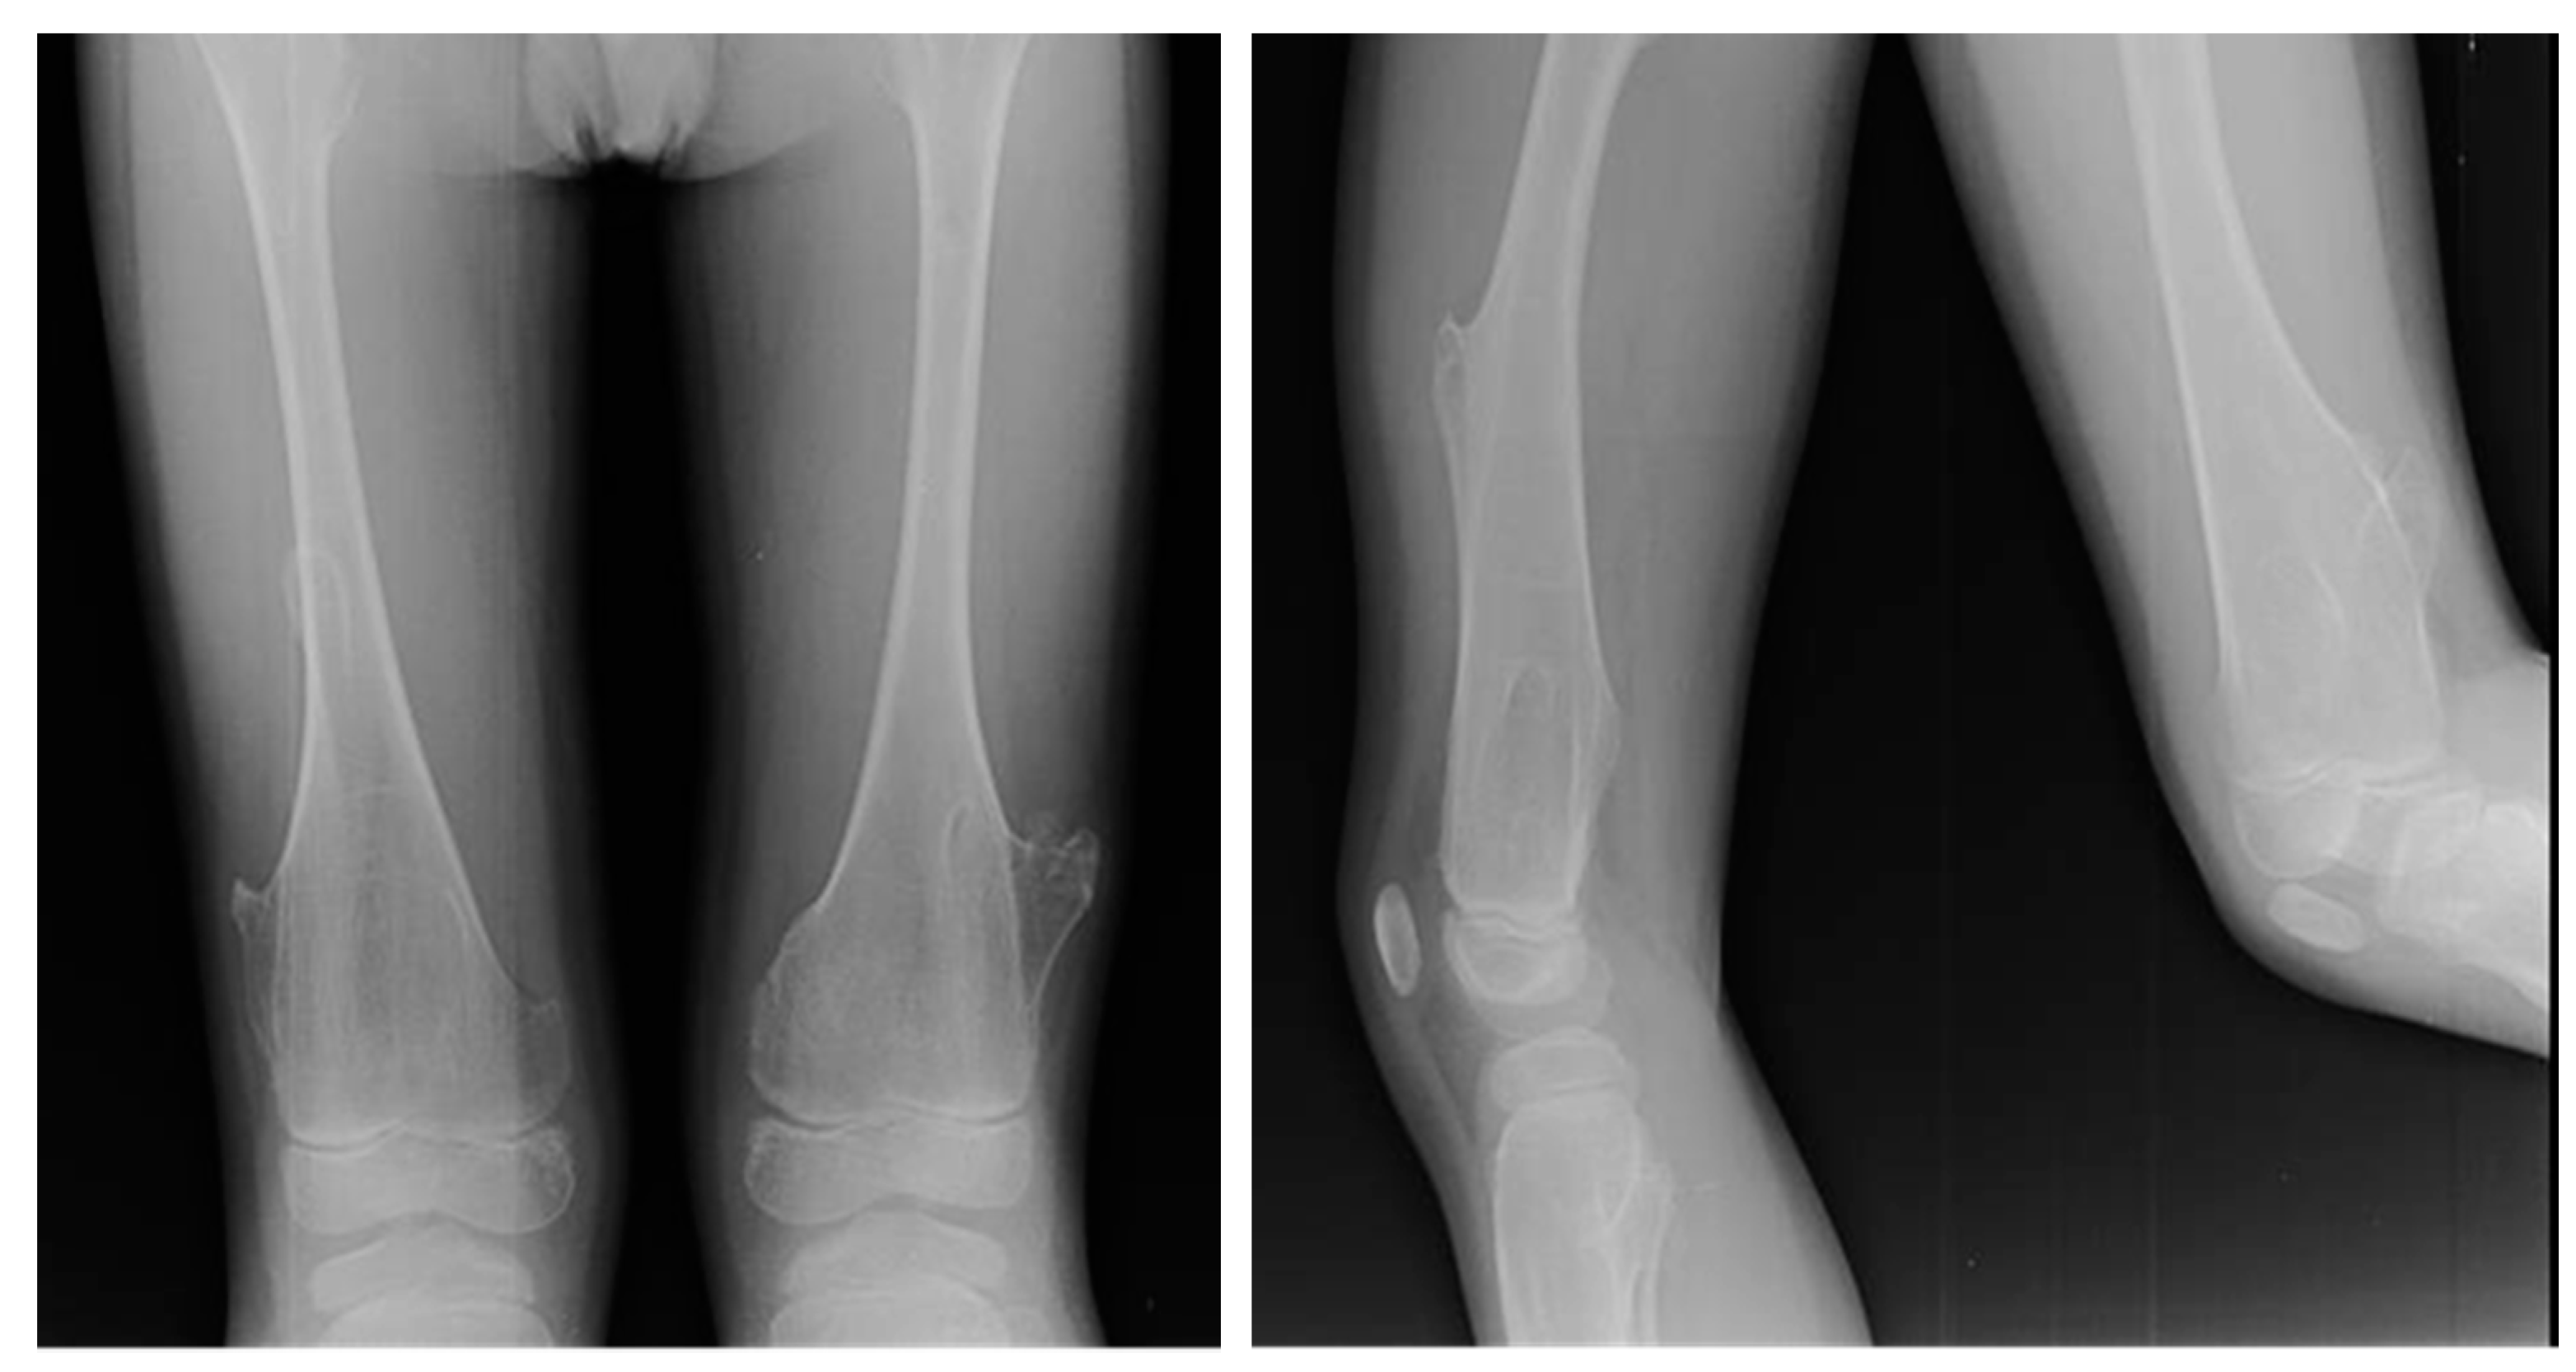

Figure 3. X-rays of a 10-year-old patient affected by Ollier syndrome.

Ollier disease is a sporadic rare condition with a prevalence of 1 in 100,000. Enchondromas usually develop before solitary enchondroma, at around 10 years of age. Multiple enchondromas grow in the epiphyses or between the metaphysis and the diaphysis [78]. The site of development could prevent proper bone growth, enlargement of the metaphysis, and bowing of the bone.

In both diseases, there is a higher risk of malignant transformation in chondrosarcoma (40%) [81]; in detail, the risk is 35% higher in Ollier disease and 50% higher in Maffucci syndrome. Histological features of both conditions include hypercellularity and cellular atypia (Figure 3).